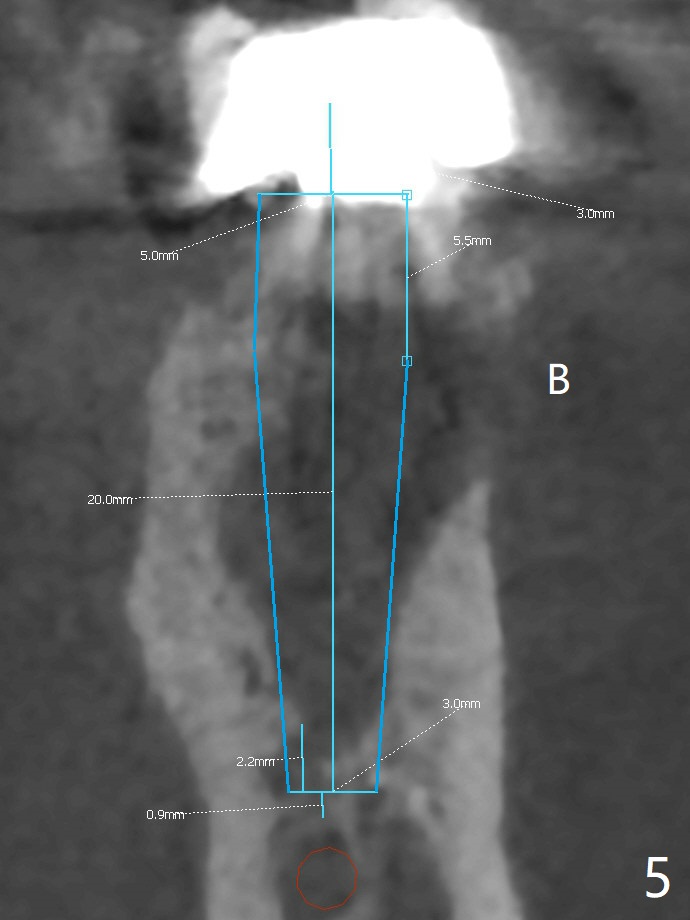

The tooth #19 of a 61-year-old man develops pain 9 years post complicated RCT (Fig.1). Periradicular radiolucency is more around the mesial root (Fig.2) than the distal one (Fig.3). Section the crown to check whether the distal margin is restorable. Remove the mesial root to determine whether the distal one is salvageable or not. If not, place a 5x15 mm bone-level implant with guide. To reduce the chance of screw loosening, consider placing a tissue-level implant (Fig.4,5). Preserve the buccal crestal bone (Fig.6 *) during extraction and debridement, which keeps the socket open for bone graft and healing. Draw blood for PRF PRN for membrane and sticky bone.